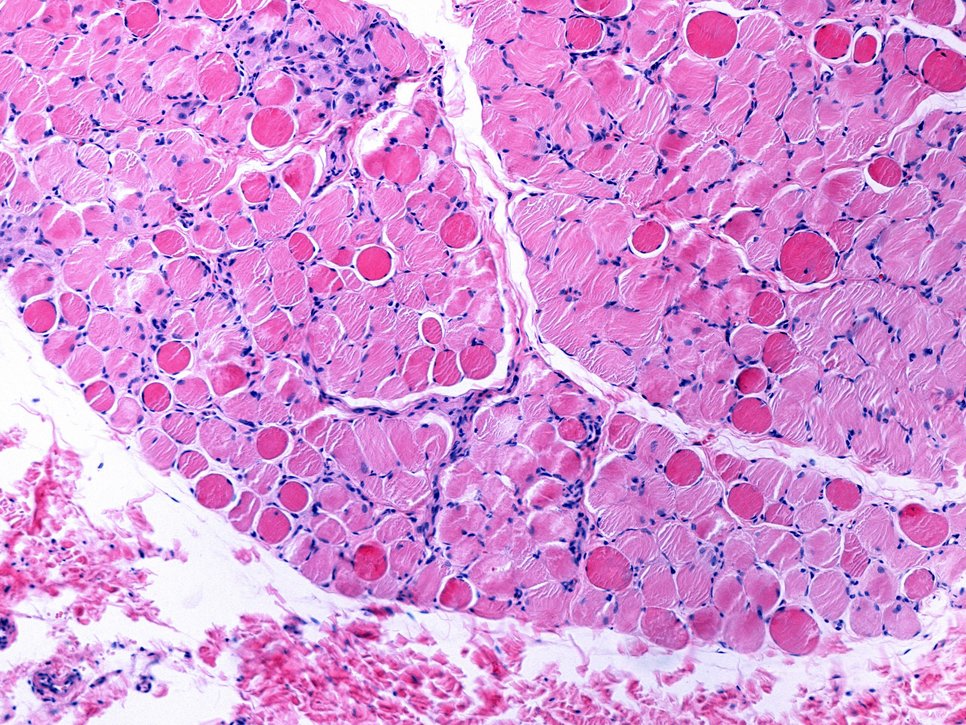

Bei der Duchenne Muskeldystrophie (DMD) handelt es sich um eine schwere Muskelerkrankungen, die vor allem Jungen betrifft. Die Erkrankung verläuft chronisch und beginnt bereits im Kindesalter. Die Lebenserwartung bei den betroffenen Patienten ist deutlich verkürzt. Verursacht wird die bislang nicht heilbare Erkrankung durch Mutationen im Dystrophin-Gen. Dieses liegt auf dem X-Chromosom. Dystrophin ist für die Stabilität der Zellmembran in Muskelfasern wichtig. Durch den Gendefekt fehlt den Patienten Dystrophin, so dass die Muskelzellen in ihrer Funktion eingeschränkt sind und die Muskulatur zunehmend geschwächt wird.